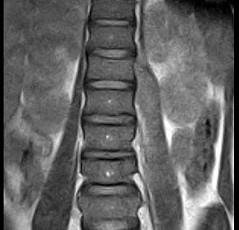

问题 女,9岁,背部隐痛,发热1个月余,MRI检查如图,请选出最可能的诊断 ( )

选项 A、脊椎结核伴硬膜外脓肿 B、椎体压缩骨折 C、脊柱转移瘤 D、硬膜下血肿 E、化脓性脊柱炎

答案 A